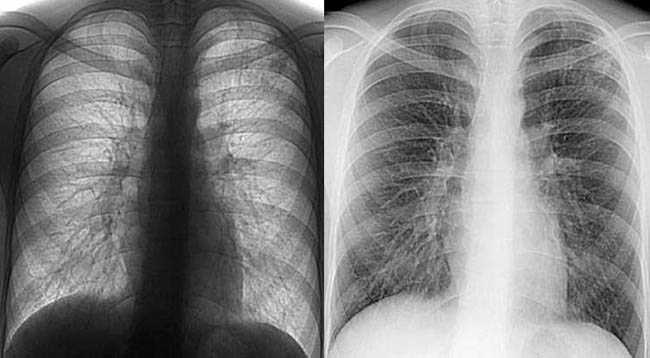

Рентгеновский анализ развеет ваши сомнения

По словам главного врача кантона Цуг Рудольфа Аури, девочка находится в госпитале. Она поступила сюда на прошлой неделе с признаками пневмонии, однако рентгеновский анализ показал, что речь идет о туберкулезе.